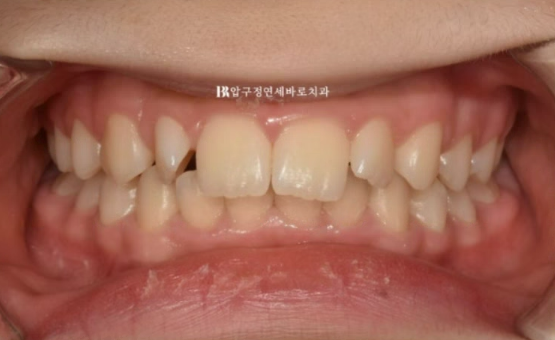

덧니교정을 위해 온 초등학생 아이입니다.

앞니가 갚게 물리는 과개교합이 보이고 앞니가 많이 돌아가 있습니다.

인비절라인 라이트는 장치 갯수가 14개 입니다.